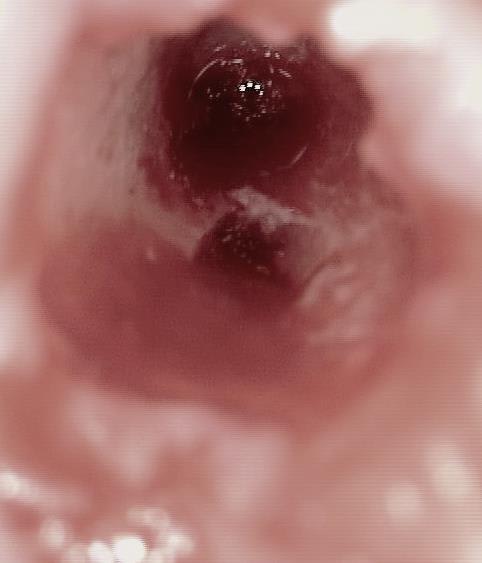

je t'explique : L'implant est un monobloc a tête carrée clavetée sur les 4 cotés la reconstruction prothétique se fait soit directement sur la tête soit par en utilisant des pieces intermediaires clavetées/cémentées que mes potes Allemands appelent les prep caps...Ca devient de la prothese conventionelle..Comme le prep caps a été placé le jour de la pose de l'implant..et que finalement faire une provisoire s'impose pas toujours..la gencive acceuille tellement bien le zicone ou le titane qu'a l'empreinte la limite usinée du prep caps peut etre recouverte..et alors.??.placer un fil ou mettre un coup de bis electrique..pourquoi faire?? on prends l'empreinte du pilier quitte à avoir un sous contour radiologique mais une excelente santé parodontale. Je te met quelques photos et ce week end je lance un post spécial sur cette technique ( Au moins 300 implants icononographiés de A à Z)

Ca marche aussi bien que les élévation de sinus en voie crestale..mais bon là aussi il vaut mieux faire vendre du biobidule ou laisser ces chirs a des "experts" vise l'augmentation osseuse obtenue sur l'implant en 16..:)